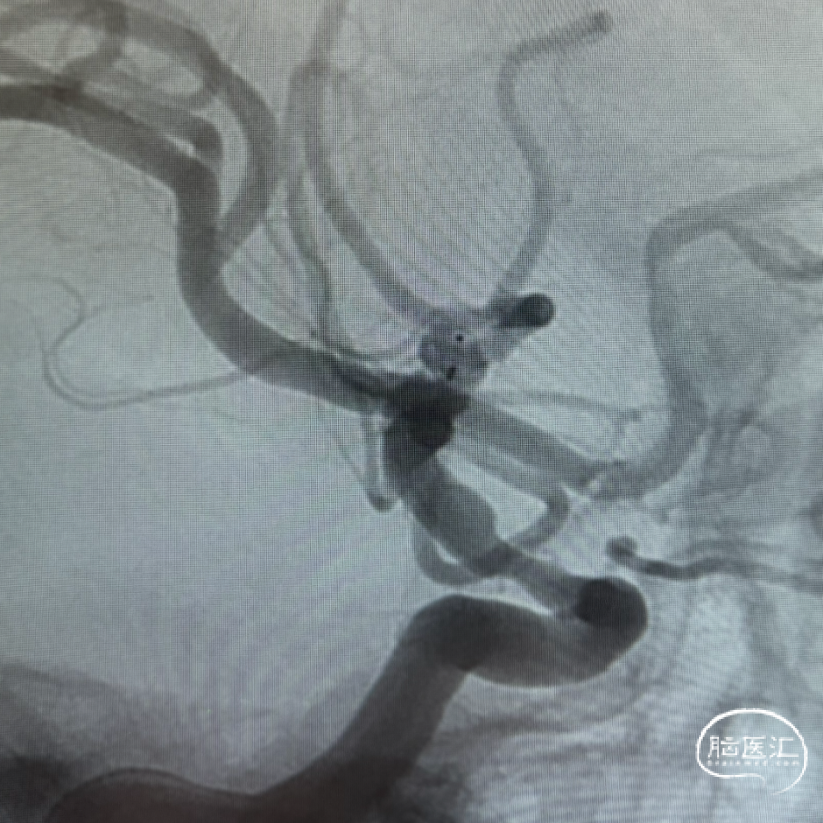

现病史:患者5月余前因头晕就诊外院,查颅内动脉CTA提示:1、左侧大脑中动脉M1段动脉瘤;2、双侧颈内动脉C5段硬化斑块,管腔轻度狭窄。3、双侧椎动脉V4段走行迂曲。MRA颈部动脉增强血管成像提示:1.左侧大脑中动脉M1段动脉瘤。2.双侧颈内动脉C5段动脉硬化伴管腔轻度狭窄。3、双侧椎动脉V4段走行迂曲。后于我院行脑血管造影提示:左侧大脑中动脉M1水平段早额支起始部动脉瘤,瘤颈3.5mm,动脉瘤大小4.4*3.5mm。为求动脉瘤介入手术入院。

三维旋转图像:左侧大脑中动脉早额支起始部囊性动脉瘤。

动脉瘤参数:最大径4.4mm,瘤高3.5mm,瘤颈宽3.5mm,载瘤动脉直径1.3mm。

工作角度造影。

本例患者为左侧大脑中动脉早额支与M1主干分叉部动脉瘤,其解剖特点显著不同于常见分叉部动脉瘤,动脉瘤瘤颈主体位于早额支,该载瘤早额支细小且与大脑中动脉M1主干成角明显,大脑中动脉M1段自身亦在动脉瘤部位向上成角,导致血管构筑和血流动力学复杂化。如选择常规支架辅助弹簧圈治疗,支架不能满意打开,支架内血栓形成的风险大大增加。故WEB™ 17自膨式动脉瘤瘤内栓塞器治疗是较为合适的介入治疗方案。术前三维重建显示动脉瘤最大径4.4mm,形态相对规则,但成角的存在使微导管塑形成为关键。对于成角显著者,需谨慎评估术中通路建立的可行性及装置稳定性,风险过高可考虑M1主干内血流导向装置植入或外科夹闭进行个体化决策。